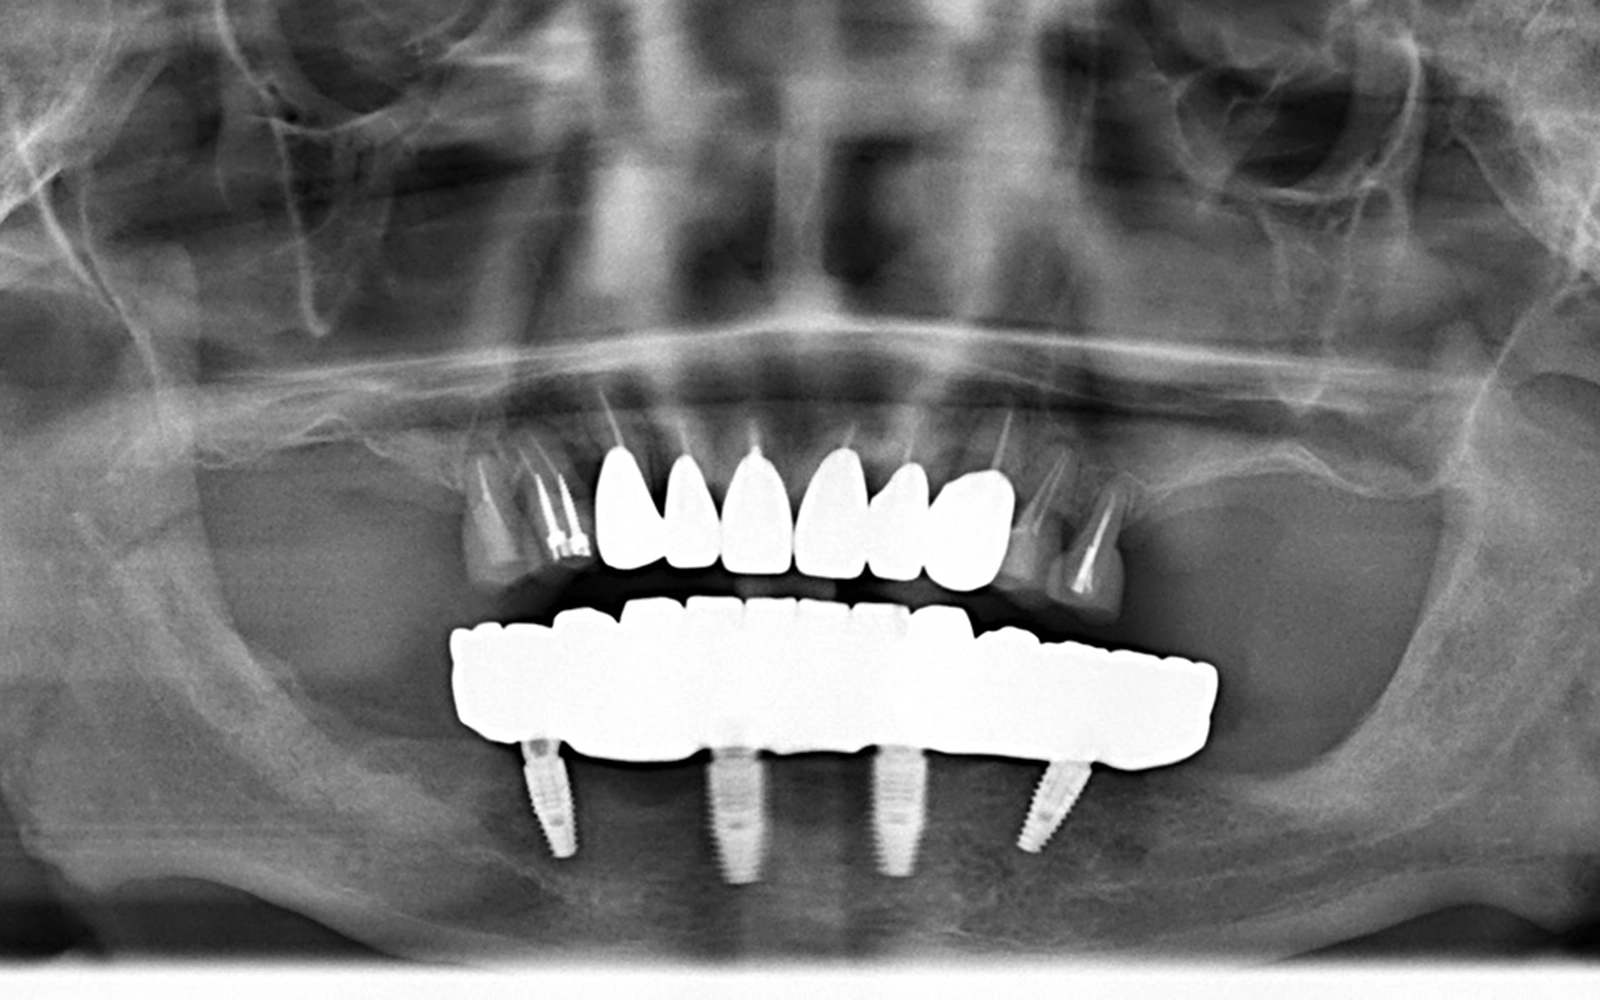

治療後は、下顎に4本のインプラント体が埋め込まれ、前方の2本は顎の骨に対してまっすぐに、後方の2本は骨の形状を活かして斜めに配置されていることが確認できます。その上に一体型の固定式の被せ物がしっかりと装着されており、骨とインプラントが安定した状態で結合していることが見てとれます。

上顎についても被せ物が整った形で装着され、上下の歯列全体としてバランスの取れた噛み合わせになりました。

インプラントと骨がしっかりと結合したことを確認した後、下顎に最終的な固定式の被せ物を装着しました。

上顎も保険診療による最終的な被せ物を装着し、上下の噛み合わせを慎重に調整して治療を完了しました。